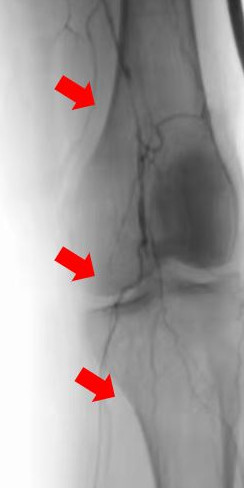

箭頭所示:右腘動(dòng)脈血栓栓塞,血流中斷

術(shù)后右下肢動(dòng)脈血流復(fù)通

箭頭所示:左股、腘動(dòng)脈血栓栓塞,血流中斷

術(shù)后:左股腘動(dòng)脈血流復(fù)通